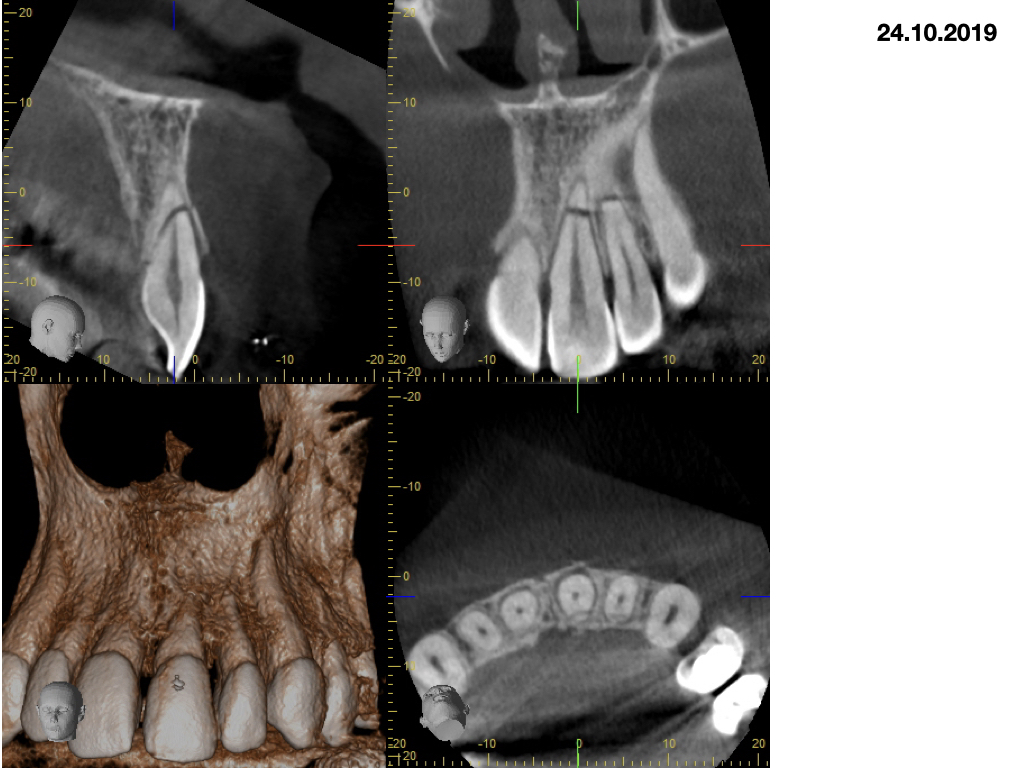

Wurzelfrakturen